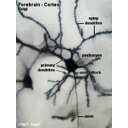

Neuronas.jpg